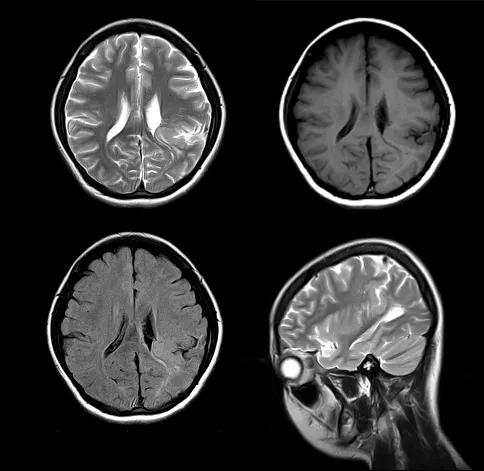

脑裂畸形

脑裂畸形 (schizencephaly) 是一种神经元移行异常而引起的先天性颅脑发育畸形,其以横跨大脑半球的脑裂为特征性表现

临床上可有癫痫、智力障碍、偏瘫、肌力下降等症状。是由于胚胎发育期间神经元分化、移行受阻造成。且常合并其他畸形,如巨脑回、灰质异位、无脑回、多微脑回和胼胝体发育不全以及透明隔缺如等

其基本影像表现为横贯大脑半球的裂隙,裂隙外端的软脑膜与内端的室管膜通过裂隙相连续,可以形成所谓的软脑膜一室管膜缝, 裂隙两旁为内折的灰质,可单侧或双侧发病

脑裂畸形分为 I 型和 II 型:I 型即闭合型或融合型脑裂畸形,为裂隙两侧的灰质层相贴或融合,裂隙关闭,裂隙中间不含脑脊液。Ⅱ型即开放型或分离型脑裂畸形,特点为内折皮层分离,形成较大裂隙与脑室相通,内含脑脊液,脑裂衬有薄膜

case 1:女,16 岁。发作性意识不清,四肢抽搐反复发作 15 年。

诊断:左顶叶脑裂畸形。